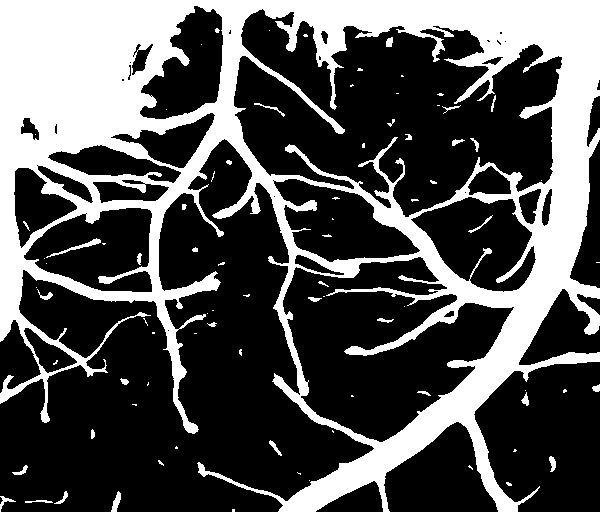

对比是否作光照补偿的二值化结果如下,可以,未作光照补偿时,二值化结果并不好,光照不均匀的地方本来是背景,也被划分为前景了。作了光照补偿则没有这个问题。

未作光照补偿的二值化结果